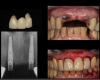

Figure 3 shows a ti-base connection, narrow emergence profile of the zirconia abutment (pink characterization), and final abutment with margins that were computer-generated and computer-manufactured to reflect the appropriate soft-tissue architecture for the patient. As shown in Figure 4, the abutment was seated and torqued to 25 Nm, allowed to rest for 10 minutes, and torqued once again to 25 Nm. The crown was tried in, fit was verified, and occlusion was established. This particular patient was concerned that the implant crown and implant would not look natural. Before beginning the single-tooth replacement with implant dentistry, a diagnostic wax-up and photographic imaging were employed to help develop a natural-looking provisional during the osseointegration phase. A treatment plan was developed and presented to the patient for considering cosmetic dentistry for tooth Nos. 6 through 11. The patient was still apprehensive and chose to begin therapy for only tooth No. 8. Since the final seat date, the patient has been very satisfied with the results of the single-tooth therapy and has committed to completing the cosmetic dentistry services for tooth Nos. 6 through 11.

Fig 3. 0 degree, milled characterized hybrid zirconia abutment with a Ti-base connection. Note the narrow emergence profile of the zirconia

abutment (pink characterization) and final abutment with margins that were computed-generated and computer-manufactured to reflect the

appropriate soft-tissue architecture.

Figure 3

Fig 4. Seated abutment (left) and crown try-in (right).

Figure 4